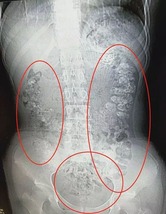

【画像】 14歳少女、胃から肛門までタピオカが詰まって緊急入院

緊急入院の14歳少女 胃から肛門までタピオカ100個発見!中国・浙江省

若い女性の間で人気沸騰中のタピオカミルクティー。1990年代、2000年代のふたつのブームを経て、現在は第3次ブームと言われるほど、毎日のように新しい店が誕生しているが、中国・浙江省では先月、14歳の女の子が腹痛を訴えて緊急入院した。

何日間も排便がなく、腹部CTスキャン検査を実施した結果、胃から腸、肛門まで100個以上のタピオカパールが数珠つなぎに詰まっていたという!